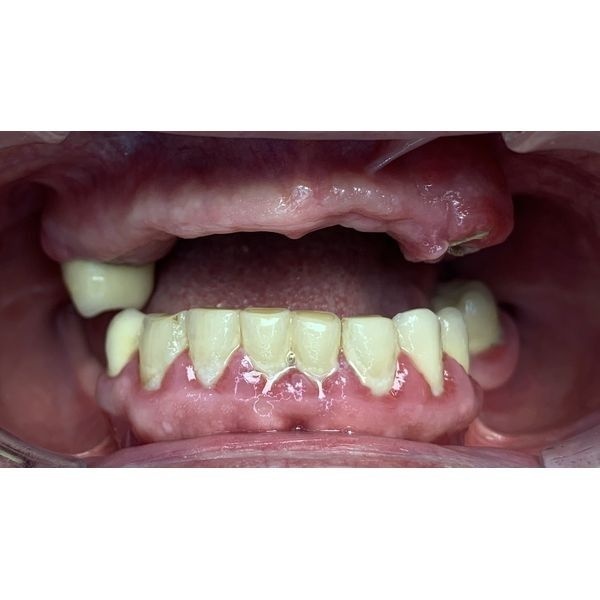

Пациентка рассказала, что у неё нет большинства зубов, а оставшиеся сильно шатаются, также её беспокоила кровоточивость дёсен. Из-за этого у женщины появились проблемы с дикцией и питанием, что негативно повлияло на работу желудочно-кишечного тракта.

Отсутствие зубов также отразилось на её внешнем виде. По словам пациентки, у неё опустились уголки рта и появились глубокие морщины, из-за чего она выглядела старше своих лет.

Слизистая рта и мягкие ткани отёчны, тёмно-красного цвета. Зубы подвижны, вокруг них отделялась гнойная жидкость.

Пародонтоз 3 (тяжёлой) степени. Оголение корней зубов на две трети. Частичная вторичная адентия верхней и нижней челюсти. Хронический периодонтит верхнего правого и нижнего левого зуба.